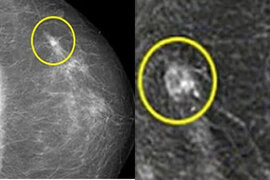

Onkoloq süd vəzisi xərçənginin əlamətlərini sadaladı

Süd vəzisi xərçəngi qadınlarda ən çox yayılmış xərçəng növlərindən biridir. Təəssüf ki, xəstəliyin diaqnozu daha çox sonrakı mərhələlərdə aşkarlanır. Rusiyadan olan onkoloq-mammoloq Marqarita Maqdalyanovanın sözlərinə görə, mütəmadi olaraq özünü müayinə etməklə yenitörəməni vaxtında aşkar etmək olar